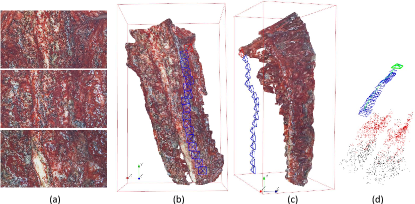

In order to evaluate the quantified accuracy of our 3D reconstruction method, we used the CT imaging of tissues as the gold standard. In this experiment, CT scans of four ex-vivo porcine livers and three kidneys were obtained (Siemens Somatom, Erlangen Germany) with a 0.6 mm resolution at our hospital, and we used the 3D Slicer software to segment the tissue models from the CT images, as shown in Fig. 9. We captured stereo videos of the tissues with the KARL-STORZ stereo laparoscope, the details of which are in Tab. II. Surfaces of livers and kidneys are very smooth and have low textures, but the proposed method was still able to reconstruct the 3D models, as shown in Fig. 7. To quantify accuracy, we registered the 3D reconstructed model with the CT segmentation results by first manually selecting landmarks, such as tissue tips, edge points and other recognizable points, and then refining the registration with the ICP algorithm. As shown in Fig. 7 (a), the root mean square errors (RMSE) with the liver cases are 1.3, 1.1, 1.4 and 2.0 mm respectively. The fourth liver case has a relatively larger error because we used an entire piece of liver and the video was captured at a larger camera-tissue distance. The results on porcine kidneys are shown in Fig. 7 (b), the RMSE of which are 1.0, 1.0 and 1.1 mm respectively. The histograms of errors are also provided in Fig. 7, which show that most points have an error of less than 2mm. It is worth noting that there are multiple sources of errors, including 3D reconstruction error, CT resolution error, CT segmentation error and registration error that contribute to the obtained RMSE in this experiment. In addition, because the livers and kidneys were placed on a textureless plastic sheet and part of the sheet were also included in the 3D reconstructed model, which is difficult to be totally removed (see the tissue edges in the distance maps of Fig. 7), so the quantified error may also include a small amount of the background. Therefore, it is a reasonable assumption that the actual error of our 3D reconstruction method is smaller than the reported RMSE.